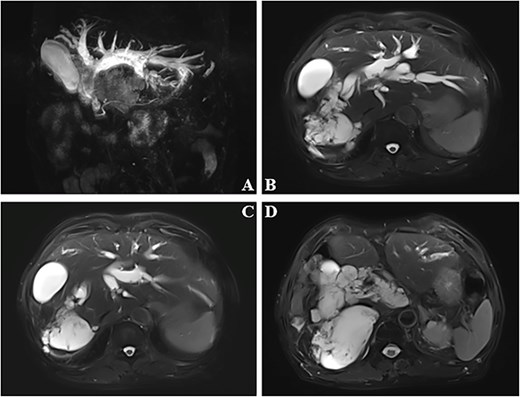

During surgery, extensive abdominal adhesions were observed. Fused lymph nodes were noted in the hepatic hilar region. The gallbladder was deformed due to compression by the dilated common bile duct and the lesion in the right hepatic lobe. The gallbladder was removed and the common bile duct was opened, revealing a large amount of mucoid material and stones spilling out. Intraoperative frozen section pathology confirmed the diagnosis of biliary mucinous adenocarcinoma (Fig. 2). After meticulous adhesiolysis, a left hepatic duct-jejunostomy was performed. Postoperatively, the patient’s bilirubin levels decreased significantly. Follow-up abdominal CT showed marked reduction in biliary duct dilation compared to previous imaging. Survival follow-up is ongoing.

The tumor contains abundant mucin with floating adenocarcinoma cells (A–C). Chronic inflammation of the gallbladder without evidence of carcinoma involvement (D).